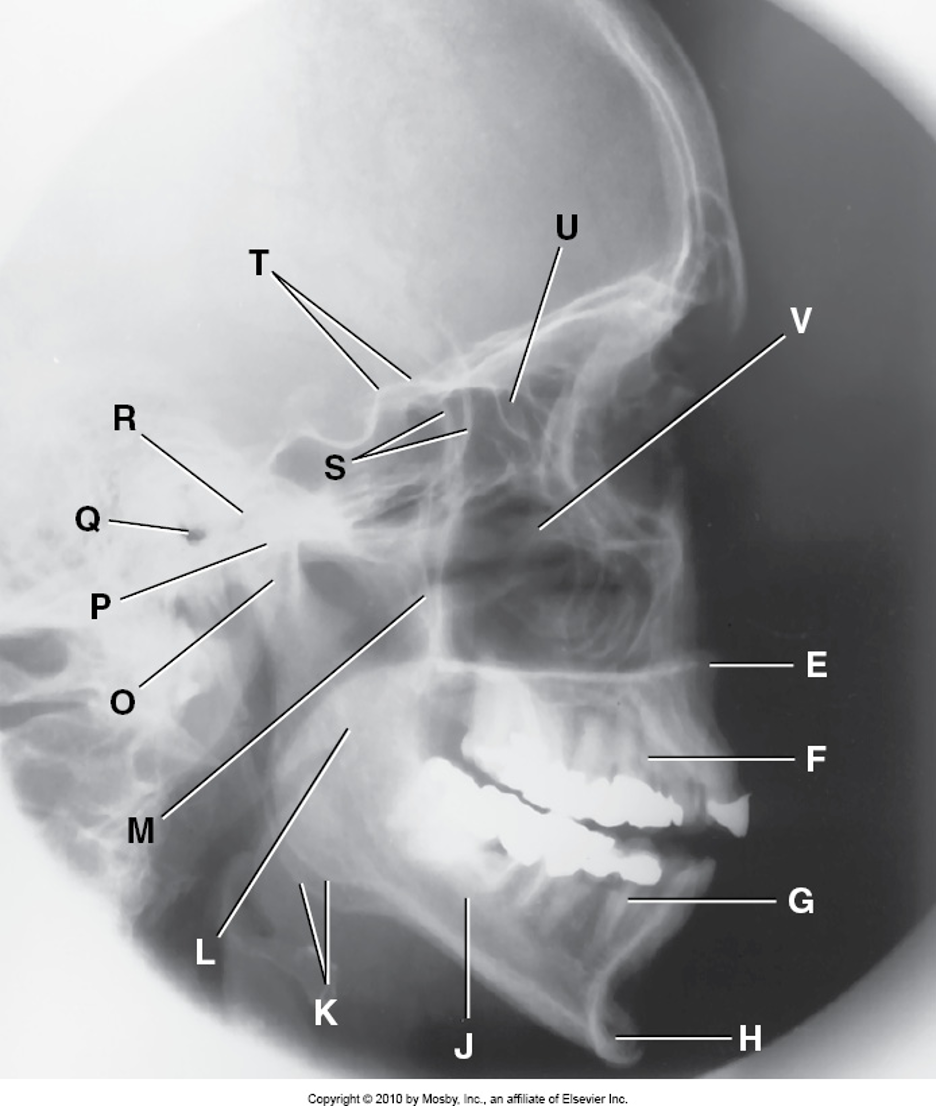

E

Anterior Nasal Spine

F

Alveolar Process of Maxilla

G

Alveolar Process of Mandible

H

Mentum or Mental Protuberance

J

Body of Mandible

K

Angle of Mandible (Gonion)

L

Ramus of Mandible

M

Coronoid Process

O

Neck of Mandibular Condyle

P

Condyle or Head of Mandible

Q

EAM

R

Temporomandibular Fossa of Temporal Bone

S

Greater Wings of Sphenoid

T

Lesser Wings of Sphenoid with Anterior Clinoid Process

U

Ethmoid Sinuses Between Orbits

V

Body of Maxilla Containing Maxillary Sinuses